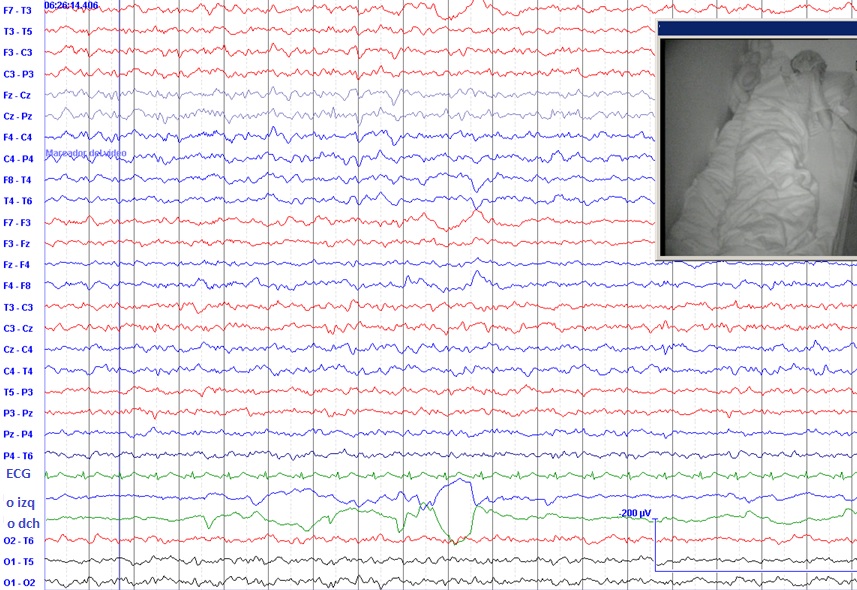

Posteriormente, en 1953, Nathaniel Kleitman descubrió que el sueño nocturno era de dos tipos: pasivo o NREM (sin movimientos oculares rápidos); y activo o REM (con movimientos oculares rápidos) Figuras 1 y 2 .

Al estudiar entonces las crisis epilépticas que se producían durante la noche se vio que el 95 % de ellas ocurrían durante el sueño pasivo o sueño NREM. El sueño NREM está formado a su vez por fases de sueño más o menos” profundo”. En aquel entonces se clasificaban (según el grado de profundidad) en fase NREM-I; NREM-II; NREM-III; y la más profunda de todas, NREM-IV. Se observó que casi todas las crisis epilépticas ocurridas durante el sueño aparecían en las fases NREM-I y NREM-II.

Posteriores estudios han confirmado la casi ausencia de crisis epilépticas durante el sueño activo o REM.

Como el sueño NREM está formado por ondas más sincronizadas que el sueño REM, que se llamó “sueño de la actividad electroencefalográfica desincronizada”, siempre se ha pensado que la desincronización del EEG sería un factor protector frente a las crisis epilépticas.

La privación del sueño se utiliza frecuentemente como método de activación del EEG en las epilepsias. Es más probable que encontremos en el EEG las alteraciones características de la epilepsia si el paciente no ha dormido bastante. Esta peculiaridad es muy útil cuando estamos intentando hacer el diagnóstico, pero también es la base de la recomendación que hacemos siempre a nuestros pacientes: duerma bien.